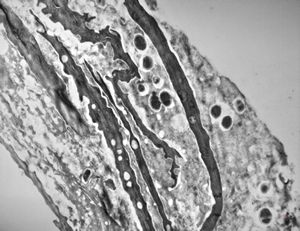

F, 1m. | sepsis - mycotic dermal lesions

M, 57y. | dermal mycotic lesion

M, 57y. | dermal mycotic lesion … toluidine-blue stained semithin section